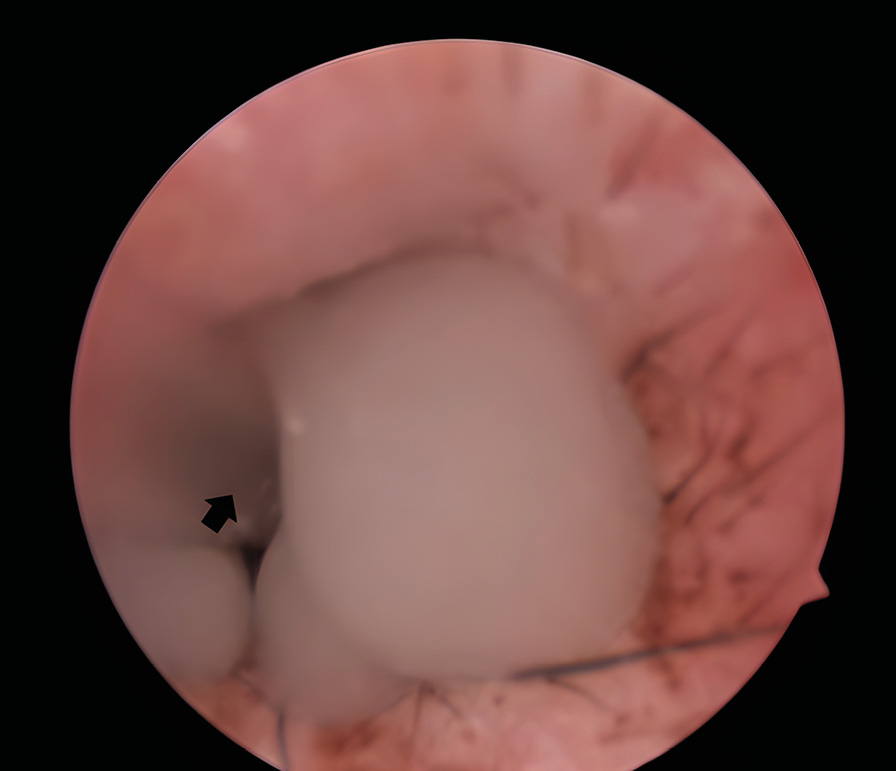

La membrana timpánica consta de dos secciones: la pars flaccida (más pequeña) dorsalmente y la pars tensa (más grande) ventralmente. En la superficie medial de la pars tensa se inserta el manubrio del hueso martillo, que se visualiza externamente como la estría del martillo (estria mallearis) (imagen 1).

No obstante, en algunos pacientes con otitis media, la membrana timpánica puede mantenerse íntegra, aunque mostrando alteraciones tales como opacidad, cambios en la coloración (de blanco perlado a grisáceo), abombamiento o presencia de líquido (exudado purulento o mucoide) o formaciones carnosas (como pólipos o neoplasias) detrás de la membrana.

La presencia de abundante secreción mucoide o mucopurulenta en el conducto auditivo externo, junto con la observación de neutrófilos con cambios tóxicos y bacterias en las citologías del conducto auditivo horizontal, sugiere de manera significativa la existencia de otitis media. El diagnóstico se confirma si se detecta la rotura parcial o la ausencia completa de la membrana timpánica.